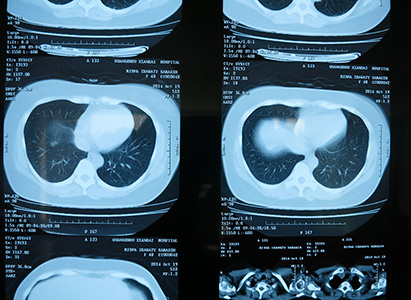

So far, Risma Idawaty Saragih have underwent four times of interventional therapy, one time of radiotherapy, and one biological immunotherapy. As all those treatments were minimally invasive treatments, Risma Idawaty Saragih did not feel much discomfort. According to her, the doctor who performed the interventional therapy for her was very experienced: the trauma was very small and there were few side effects. She did not lose much hair, no vomit, her appetite was very good, and she even gained 3kg after the treatment. The curative effect was also very good. In the admission diagnosis it said there were recurrences in liver and lungs, but after treatment tumors in the liver disappeared, only some were remained in the lungs. CT results showed that the bladder distorted due to pressing of tumors has also restored to normal shape, so the abdominal pain which had long plagued her disappeared. As a result, her defecation also returned to normal and the sleep was acceptable.